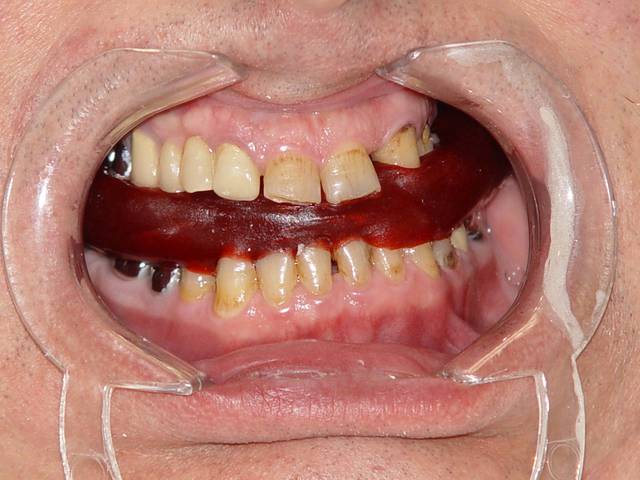

que feriez vous dans ce cas, les photos parlent d'elles mêmes

bon, si tu as besoin de plus d'explications, le patient aimerait ne plus se mordre la gencive vestibulaire...

Si le patient ne veut plus se mordre la gencive, il faut la lui enlever.

Cela dit, ta photo en occlusion montre qu'il ne se la mord pas (en tous cas pas la gencive).